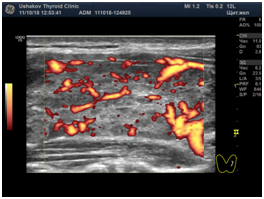

Note that the written Ultrasound Protocol must accompany the images, some of which must be in the "vascular" mode, which are called CDK (color Doppler mapping) and EDK (energy Doppler mapping).

In addition, in order to accurately assess the magnitude of blood flow during ultrasound of the thyroid gland, the sonologist must correctly configure the ultrasound machine. If the settings are incorrect, you can get a distorted result, which often happens in medical facilities at any level (from laboratories to the ESC).